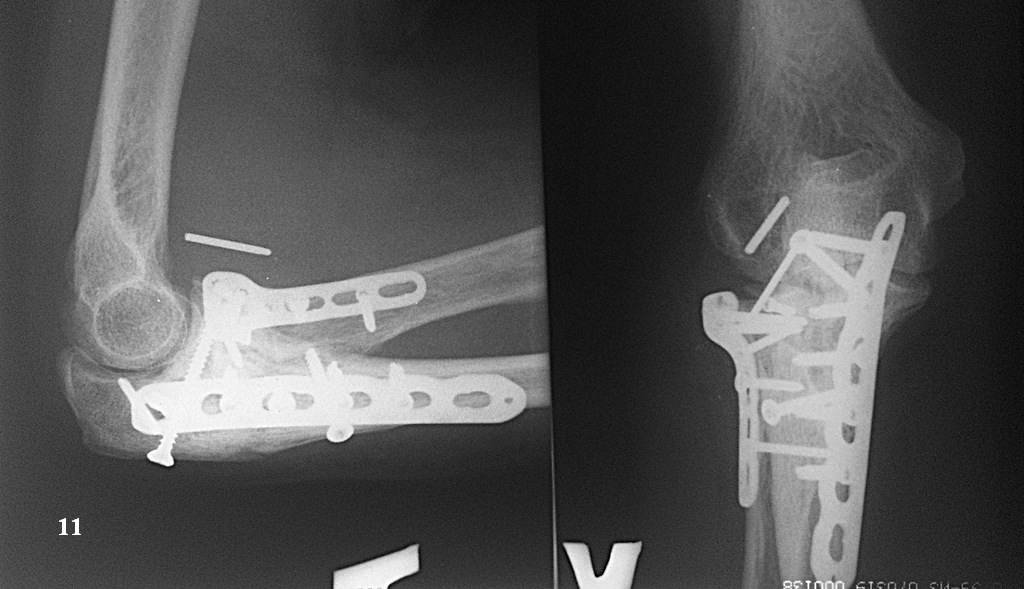

Казалось бы все счастливы, но в середине мая этого года (6 месяцев после операции) со слов больной: "Сидела на кресле, ничего не делала. И тут "щелк" в локте, с болью и легким хрустом при ротации предплечья". На снимке (рис. 10) перелом блок. винта из пластины на головке луча и миграция оставленной спицы. Скиаграмма для наглядности (рис. 11). Посоветовали ограничить движения, обезболивание. и сделать контроль через 3 недели.

Через три недели (7 месяцев после операции) вот такая картина (рис. 12). Блок. винт нашел свою "гавань" и затормозил возле локтевого отростка снаружи. А вот спица продолжает путешествовать и полностью вышла из головки в сторону наружной поверхности локтевого сгиба (рис. 13). При этом боли ушли, хруста нет, объем движений вот по этой ссылке: http://youtu.be/S4JK_Gpzaos